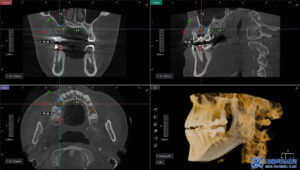

임플란트 식립 전에는 CT 촬영을 통해

뼈의 두께와 높이,

신경과의 거리 등을

정밀하게 확인했습니다.

CT 결과를 바탕으로 식립 각도와

깊이를 세밀하게 계획하고,

충분한 뼈 지지가 확보될 수 있도록

맞춤형 임플란트 계획을 수립하였습니다.